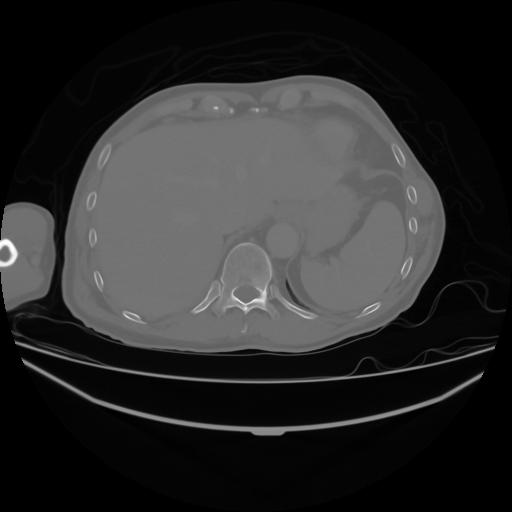

4 CUERPO,CE,Axial,3.0,CUERPO,,